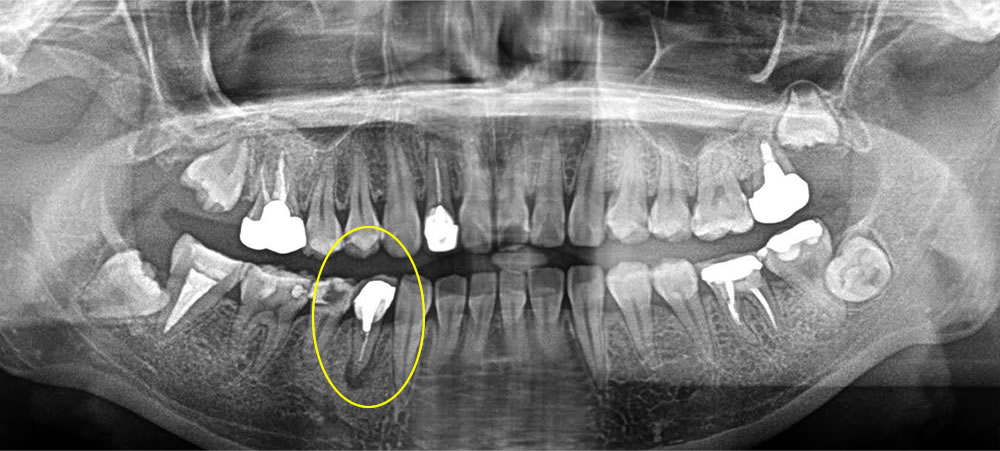

根尖性歯周炎の歯を抜歯即時埋入インプラントで治療した症例

年齢

50代

性別

男性

症例を見る